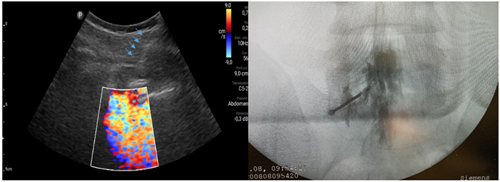

Pacientes y métodos: Un total de 25 pacientes con dolor radicular lumbosacro fueron seleccionados para recibir inyecciones epidurales interlaminares de esteroides en posición decúbito dorsal, utilizando la técnica ecoguiada en plano, en tiempo real, en eje corto o transversal. En todos los casos, un epidurograma de control fue realizado previo a la inyección de la solución de esteroides. El rendimiento de la técnica fue estudiado mediante la tasa de éxito de la misma, entendido como éxito a la obtención de un epidurograma sin necesidad de abandonar la técnica ecográfica en un tiempo menor a 10 minutos. El rendimiento del procedimiento fue estadísticamente evaluado por el método de la suma acumulativa (CUSUM), y la curva de aprendizaje aplicando este método fue construida.

Resultados: La distancia promedio desde la piel al complejo posterior evaluada por el escaneo ecográfico previo al procedimiento fue de 6,7 ± 1,8 cm. De los 25 procedimientos realizados, en 21 se alcanzó el espacio epidural sin ayuda de la fluoroscopia, en un tiempo promedio de 4,8 ± 1,2 minutos. Esto constituye una tasa de éxito del 84 %. En los cuatro procedimientos restantes el espacio epidural fue alcanzado con éxito mediante el uso complementario de la fluoroscopia.